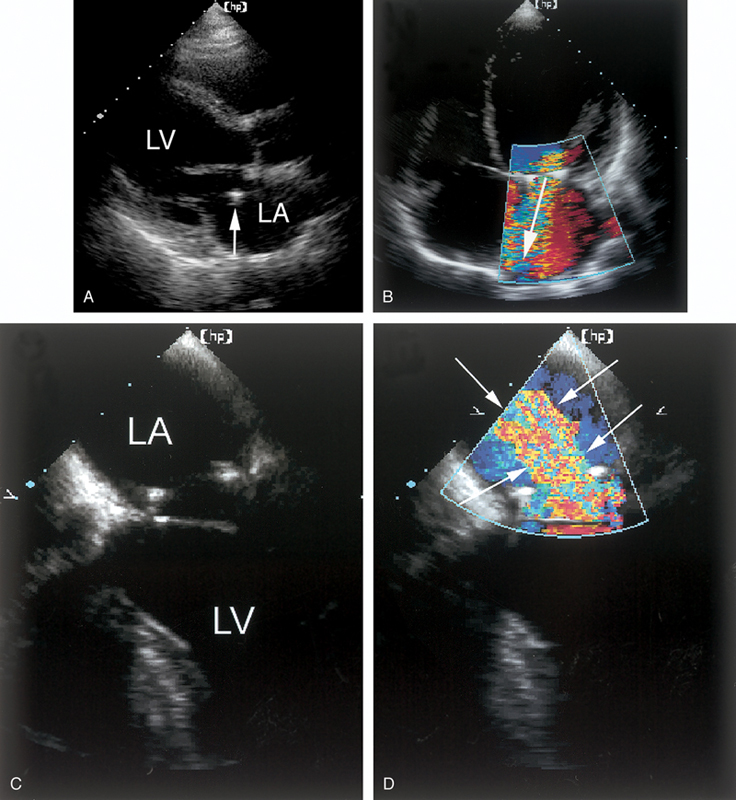

فحوصات تشخيصية لبعض امراض القلب والشرايين التاجية